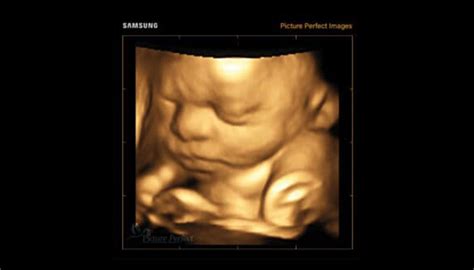

Ecografia 3D și 4D reprezintă tehnologii avansate de imagistică utilizate în timpul sarcinii pentru a oferi imagini detaliate ale fătului. Ecografia 3D utilizează ultrasunetele pentru a crea imagini tridimensionale ale fătului. Astfel, se obține o imagine mai clară a structurilor anatomice fetale. Ecografia 4D este o formă avansată de ecografie 3D, care adaugă elementul de timp, oferind imagini în mișcare în timp real. Practic, ecografia 4D creează un video al fătului în mișcare, permițând observarea expresiilor faciale și a activităților fetale în direct. Comparativ cu ecografia clasică, 2D, cele două variante mai performante au avantajul că oferă imagini mai clare și mai detaliate ale fătului. Astfel, aceste forme de ecografie devin extrem de utile pentru a oferi viitorilor părinți o imagine a ce înseamnă malformația fetală descoperită și evoluția acesteia. Este important de menționat că imaginile detaliate furnizate de ecografiile 3D/4D pot ajuta medicii să planifice intervenții medicale prenatale sau postnatale necesare. Acestea oferă o înțelegere mai bună a problemelor medicale, astfel că simplifică procesul de diagnostic. În plus, prin intermediul ecografiei 3D sau 4D, conexiunea dintre părinți și făt se consolidează. Este foarte important pentru părinți să-și vadă mai bine copilul, această procedură oferindu-le o oportunitate unică de a se conecta emoțional cu fătul lor înainte de naștere.